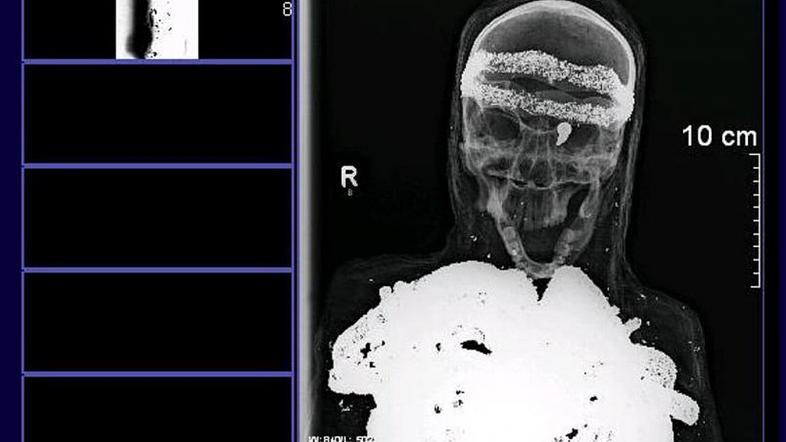

Magnetna resonanca je pokazal, da je človeška lobanja relativno dobro ohranjena, iz leve očesne jamice pa štrli puščica. Uganko še povečuje posmrtna maska in to, da  je rentgen pokazal kovinske plasti, ki prekrivajo kosti 1,49 metra dolgega bitja. Spola niso mogli potrditi. "Porajajo se le nova in nova vprašanja," je dejal Lutz-Wolfgang Kettler, oče dečka, ki je našel sarkofag. K temu prispeva tudi dejstvo, da so povoji novejšega datuma – izdelani so bili strojno v 20. stoletju, poroča AFP.

Patolog Andreas Nerlich je za spletni Spiegel dejal, da so lobanja in kosti resnične, vendar pa je mumija kot taka "neprava, sestavljena iz enega ali več teles". Policija bo počakala poročila vseh strokovnjakov, ki bodo tudi pokazala, ali morda ne gre za antično mumijo, pač pa za čisto sodobni umor.